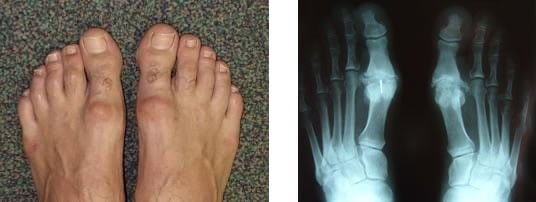

Masz ograniczenia ruchomości w obrębie palucha? Odczuwasz ból w dużym palcu podczas chodzenia? Pojawił się obrzęk? Możesz cierpieć na schorzenie występujące pod nazwą paluch sztywny (hallux rigidus). Jego przyczyna związana jest ze zmianami zwyrodnieniowymi stawu śródstopno-paliczkowego palucha. W przeciwieństwie do haluksa, czyli palucha koślawego w przypadku palucha sztywnego nie występuje odchylenie palucha, czy też przyśrodkowe przemieszczenie pierwszej kości śródstopia. Ewentualnie jest ono bardzo nieznaczne.

Jak już zostało wspomniane paluch sztywny daje takie objawy jak zaczerwienienie stawu śródstopno-paliczkowego, któremu może towarzyszyć obrzęk. Poza tym, występuje ograniczenie ruchomości w obrębie palucha. Pacjenci z tym schorzeniem skarżą się też na ból palucha, który doskwiera zwłaszcza w czasie poruszania się. Jest to szczególnie odczuwalne, gdy chodzi się w zbyt ciasnym obuwiu. Paluch sztywny może również być nieco ocieplony w porównaniu do innych części stopy.